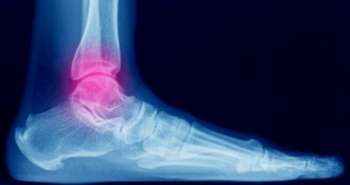

Kinesio taping could be recommended to relieve pain intensity and range of motion for patients suffering from myofascial pain syndrome at post-intervention, as revealed in a study published in 'Clinical rehabilitation'. Zhang XF et al. investigated the effectiveness of Kinesio taping for managing myofascial pain syndrome regarding pain intensity, range of motion, muscle strength, pressure pain threshold as well as disability.